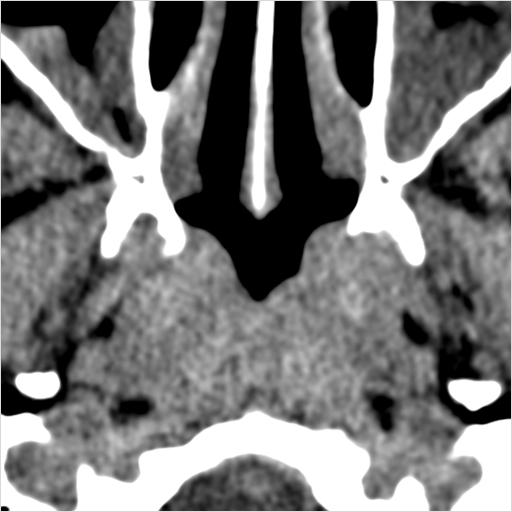

There is generalized mucoperiosteal thickening in the nasal cavity.

There is infiltration in the posterior nasal cavity or sphenoethmoidal recess that is near to or protruding into the sphenopalatine foramen and pterygopalatine fossa.

There is evidence of bone erosion along the face of the sphenoid bone or pterygoid base or processes.